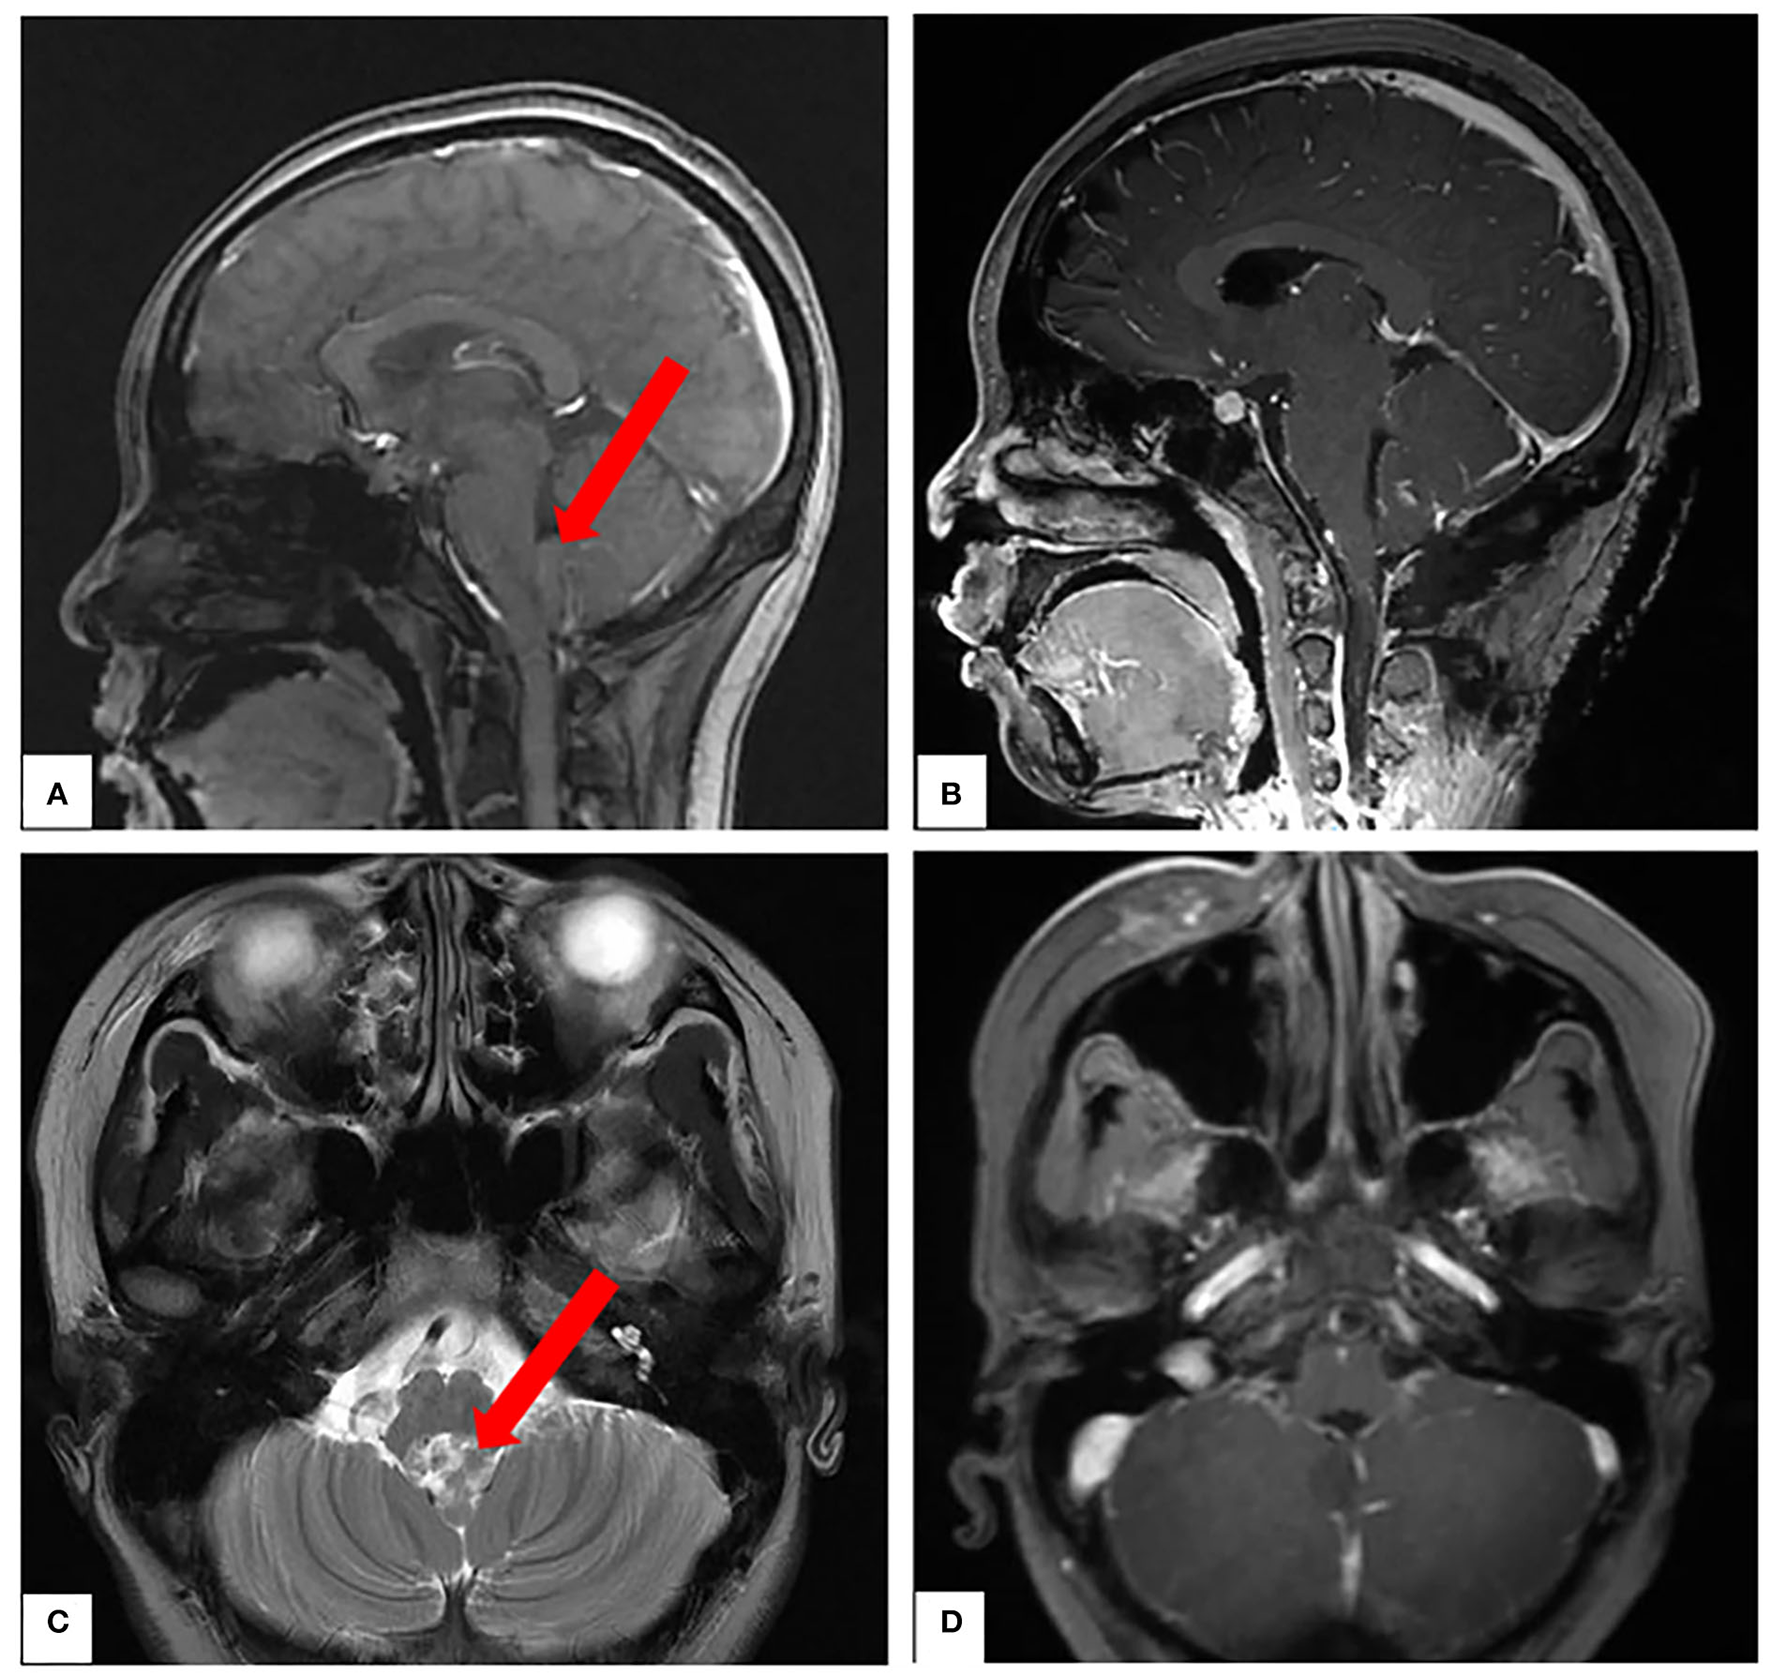

A patient in her mid-teens was found to have a space-occupying lesion in the fourth ventricle on physical examination, abutting, and squeezing the brainstem (Figure 7). She recovered well after a surgical resection in our department. According to the pathology report, it was an atypical choroid plexus papilloma. During a tumor resection, the patient's left brainstem auditory-evoked potentials (BAEP) decreased and recovered (Figure 8), which reflected that the APS tube could be used to suction out and remove the tumor without damaging the brainstem by maintaining the ideal tip negative pressure (Supplementary Video 1).

Figure 7

(A,C) Preoperative magnetic resonance imaging (MRI). (B,D) Postoperative MRI.